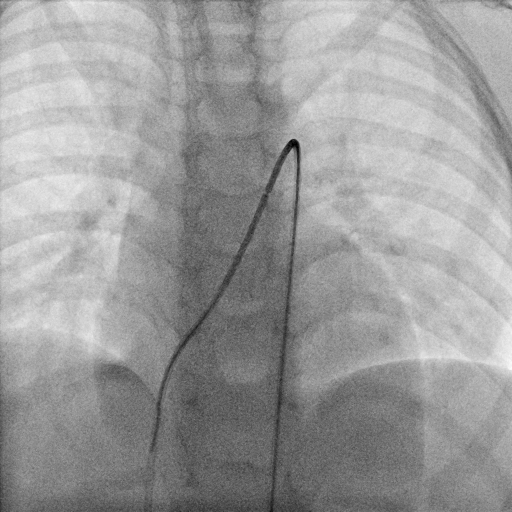

Through the femoral vein, a 5-Fr multipurpose A catheter (MP-A catheter, Cordis) was used in an attempt to cross the PDA from the MPA directly or with the assistance of a guidewire. If the antegrade approach was not successful after more than 5 minutes, operators switched to the kissing-catheter method. The antegrade catheter was left in the middle of the MPA. From the femoral artery, another 5-Fr MP-A catheter (retrograde catheter) was introduced to the descending aorta and advanced through the PDA to the middle of the MPA directly or with the assistance of a guidewire. Under a 30° cranial with 15° left anterior oblique (LAO) fluoroscopic projection, operators manipulated the antegrade and retrograde catheters simultaneously so that their distal ends would dock with each other tip to tip. A 260-cm, 0.035-inch exchange guidewire was sent from one of the catheters to another, through the docking-junction, and externalized from the proximal end of the catheter. Then, an artery-PDA-vein guidewire loop was established (Figures 1-3; Videos 1 and 2).

The kissing-catheter technique is also based on the retrograde approach but avoids the snaring operations. This method is similar to the kissing microcatheter technique previously described for percutaneous coronary intervention,7 but has not been used for PDA closure before because it seems difficult to dock the distal ends of 2 small lumen catheters in the relatively wide 3-dimensional space of the MPA. However, due to its shape and inherent stiffness, when a MP-A catheter reaches the MPA from the femoral vein, in most cases, its front end tends to press against the top wall of the MPA, pointing to the pulmonary artery bifurcation. Likewise, when a MP-A catheter reaches the MPA from the descending aorta through the PDA, in most cases, its front end also tends to contact the top wall of the MPA, pointing to the pulmonary valve. Then, we can manipulate the 2 end-to-end catheters to move their distal ends on the 2-dimensional surface of the top wall of the MPA, and dock them with each other easily.